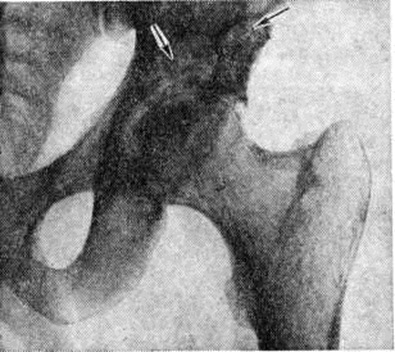

Гнойный Остеоартрит рентгенологически диагностируют только в разгар болезни, на 2—3-й неделе от начала заболевания,— обнаруживают разрушение участка метафиза кости, полное или частичное исчезновение ядра окостенения эпифиза, нарушение нормальных взаимоотношений костей в суставе, утолщение мягких тканей сустава. При этом ранняя диагностика этого тяжёлого поражения (рисунок 2) должна базироваться на соответствующей клинические, картине и данных лабораторный исследований.